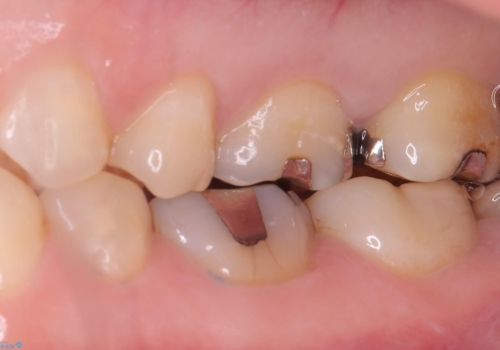

保険のメタルインレーを白くしたいということで来院されました。

左上6の近心にカリエスを認め、残存歯質と破折リスクの観点からセラミッククラウンでのやり替えとなりました。

今後ホワイトニング行う予定のため、シェード明るめにしています。